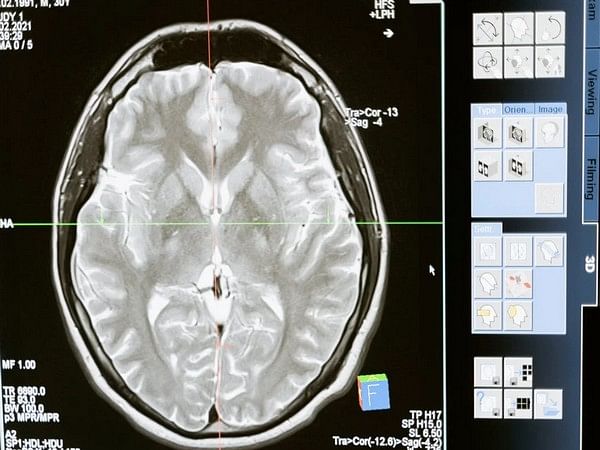

Using data from functional magnetic resonance imaging, scientists investigated dynamic functional connectivity–the way brain areas interact with one another–between neuronal populations and their link to structural white matter connections (fMRI).